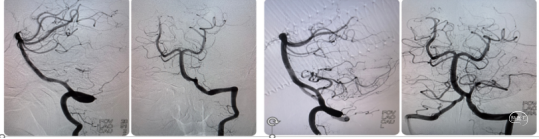

既往史:高血压病史10余年,平素不规律服药,血压控制欠佳。入院急诊心电图示:窦性心律。入院时NIHSS 19分,予以阿替普酶(50mg)静脉溶栓,直接桥接治疗。

术前CT:转入我院后急行CT检查,未见明显出血,左侧大脑后动脉条索状高密度影(图1),因患者自发病在6小时内。

手术过程:局麻,右美托咪定镇静,5F造影导管行造影检查,结果提示:左侧椎动脉相对优势,V1段连续复合弯;左侧大脑后动脉P1段中段开始远端未见显影(下图2)。

将6F 088 Neuron MAX长鞘输送至左侧椎动脉V2段中段, Powler微导管、Transend微导丝(300cm)行“首过效应”判断可见:原闭塞部位缓慢前向血流后撤出微导管,同轴交换跟进4 MAX抽吸导管(下图1)。

一次性抽吸取栓成功开通左侧大脑后动脉,造影显示左侧大脑后动脉全程显影良好,流速正常,P2段局部稍狭窄,无明显造影剂外溢(图2、3 )。

结束手术,体外见一黄白色长条状栓子(图4),股动脉穿刺至大脑后动脉再通。

术后患者镇静状态,NIHSS评分未评。

术后镇静、镇痛、控制血压,术后动态复查头颅CT见左侧枕叶、丘脑、中脑片状梗死区,无明显出血。术后予以拜阿司匹林(100mg)、硫酸氢氯吡格雷(75mg)、阿托伐他汀(60mg)。患者于术后第1天清醒,神经功能逐渐改善。

快速建立8F导引导管+CAT6中间导管建立路径,微导丝携微导管顺利通过左侧小脑后下动脉闭塞段。4/20取栓支架输送到位下图2;释放取栓支架下图3;取栓支架释放后造影血管未再通下图4。

等待5分钟后,部分回收微导管,钳夹血栓,上送中间导管,采用SWIM技术取栓,一次钳夹取出的暗红色血栓。复查造影见左侧小脑后下动脉完全再通。

术前术后对比

动态观察15分钟后,左侧小脑后下动脉血流通畅,右侧大脑后动脉远端血栓逐渐消融,持续静脉泵入替罗非班,逐级撤出各级导管,结束手术。

患者麻醉苏醒顺利,安返病房。术后查看患者意识清,言语清晰,四肢活动正常,头晕较前明显改善。继续给予内科药物治疗。次日复查CT未见出血转化,患者症状完全缓解。